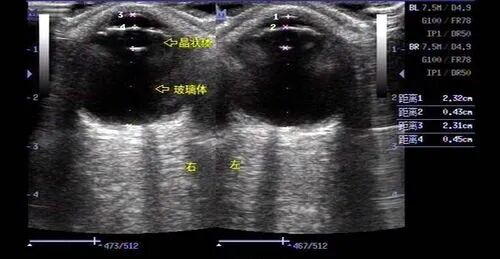

根据一线眼科临床人员的检测数据,观察到一个现象:利用生物测量仪检测哺光仪的效果,确实可以发现眼轴长度有所缩短。然而,当采用A超测量角膜至巩膜后极部的距离时,结果显示该长度并未缩短。

针对上述现象,分析认为,哺光仪照射眼睛后,其红光与红外线的热效应导致脉络膜(位于视网膜后方的血管组织)血管充血,进而使脉络膜增厚,并向视网膜前方施加压力。因此,眼轴测量结果呈现出数据偏短的现象。然而,这种由脉络膜增厚导致的眼轴缩短效应的持续性尚在研究之中,目前尚无法确定其是否具有长期持续性,亦无法判断其是暂时性还是永久性现象。